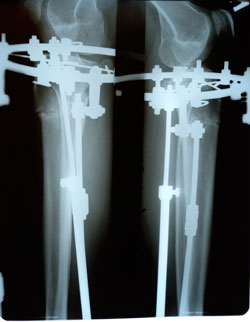

на фиксации

image-31-10-20-02-12-1.jpg

image-31-10-20-02-12.jpg